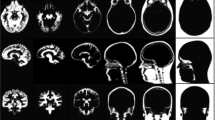

The MRI and CT data acquired in vivo are shown in Fig. 3, confirming good co-localization between the skull and 31P-ZTE signal and illustrating the bone specificity of 31P-ZTE MRI (no significant 31P signal from soft tissues). As pointed on Figs. 3c, d, 31P-ZTE seems to “miss” bone spots at the skull base (white arrow). Similarly, “red spots” can be seen outside the skull on Figs. 3b, c. Focal increase in ATP-PCr concentration or soft tissue calcification could theoretically explain these spots. However, the most likely explanation is the contribution of electronic noise, given the low SNR of 31P-ZTE images (~10). A similarity index was calculated between 31P-ZTE and CT skull images, confirming overall good co-localization (0.92 Dice index).

Figure 4 displays 18F-FDG PET images of the rat brain reconstructed with the three different attenuation correction methods. In order to illustrate the effect of attenuation correction on brain PET images, 18F activity was measured in a peripheral brain ROI for the three sets of PET images (Fig. 5). As expected for such a small animal, skull attenuation had a limited impact on brain activity. However, Fig. 5 shows that NoBone-AC underestimates 18F activity as compared with CT-AC (p < 0.001, unpaired t test). The use of 31 P-AC significantly increases brain activity as compared with NoBone-AC and overestimates brain activity as compared with CT-AC (p < 0.001).